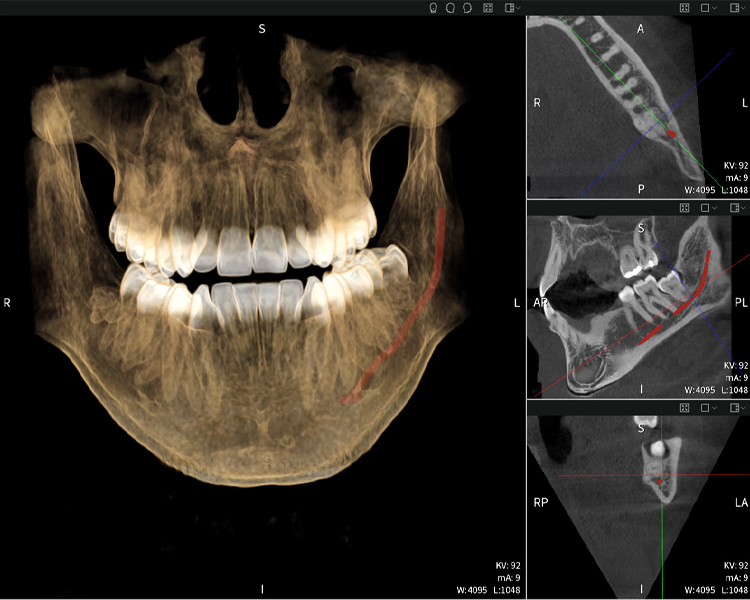

Figura d: Resultados de imagen de Seethrough Max, sobre un fondo negro.

Figura d

Las figuras b–d muestran varias vistas de una reconstrucción 3D de la mandíbula, proporcionando una visión general completa de la anatomía mandibular, la posición de los nervios en relación con los dientes y permitiendo evaluar la simetría y alineación dentaria.